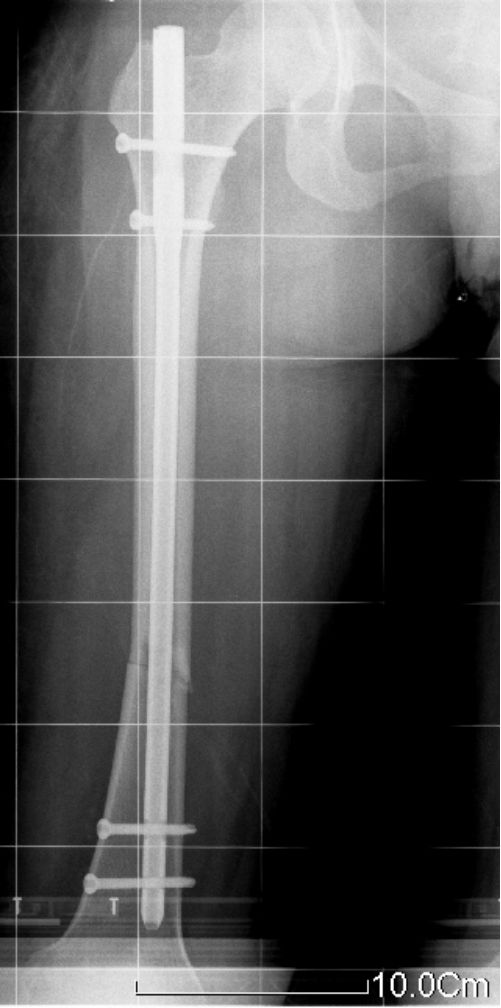

交锁髓内钉有较好的抗旋转、抗压缩作用,固定稳定性好,符合生物学固定原则(BO),在四肢长骨中应用广泛。

股骨粗隆下2cm距膝关节9cm以上的各种类型骨折。

固定骨折的力臂比钢板长,作用力均匀分散在整个骨干的中轴上,不易发生折弯变形。

锁钉使骨干从上到下形成一体,防止缩短和旋转,对骨折的固定达到最大的稳定性。